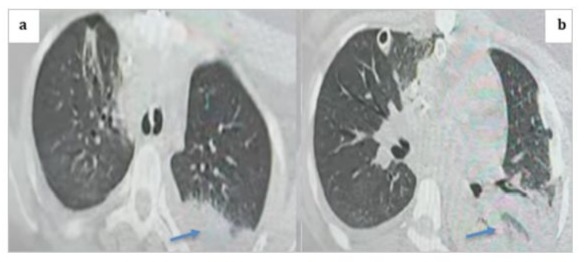

We present the clinical case of a 22-year-old female patient who underwent surgery for mitral stenosis complicated by atrial fibrillation and pulmonary hypertension. She received a mechanical valve and tricuspid valve repair. A year later, she experienced worsening symptoms. Examination revealed a thrombus on the mechanical valve. She was managed in the cardiac intensive care unit and received aspirin and heparin. Post-treatment, there was improvement in the transvalvular gradient and partial regression of the thrombus. She was discharged on acenocoumarin with regular monitoring. However, after one year (2 years post-surgery), she arrived at the emergency room with a more severe episode of acute global congestive heart failure. Upon clinical examination, crackles were detected in the lungs, along with mild hypoxia (O2 saturation 93%), and absence of fever or lower limb swelling. Blood pressure measured at 90/60 mmHg, with tachycardic atrial fibrillation (120 bpm) and a respiratory rate of 30/min. Chest X-ray revealed cardiomegaly and bilateral pulmonary edema. (Figure 1) Blood tests showed leukocytosis, elevated NT-proBNP levels (800), and moderate metabolic acidosis. Echocardiography documented near-complete blockage of the mechanical mitral valve leaflets with high transvalvular gradient and significant regurgitation. After initial stabilization with norepinephrine, heparin, diuretics, and dual antiplatelet therapy, her condition deteriorated on the fifth day with shock, hypoxia, and confusion, raising concerns about possible systemic embolisms, including secondary cerebral embolism, which was ruled out by a brain CT scan. (Figure 2) In a situation of mitral valve blood clot causing cardiogenic shock, norepinephrine dosage was increased to 15 mcg/kg/min and dobutamine started at 5 mcg/kg/min. TransThoracic Echocardiography (TTE)showed severe pulmonary hypertension, distended left atrium, high transvalvular gradient, severe mitral regurgitation, and hyperkinetic Left Ventricle (LV). Epinephrine was given, dobutamine stopped, and patient moved to operating room with equipment for perfusion and transfusion, and received vitamin K, exacyl, Vancomycin, and heating blanket.

Figure 1: Preoperative frontal chest X-ray showing bilateral basal opacities with blunting of both pleural recesses, a normal-appearing cardiac silhouette, sternal wire sutures, and the projection of the mechanical valve ring.

Figure 15: Thoracic CT scan in the parenchymal window with axial cuts showing a posterior basal left alveolar consolidation syndrome consistent with pneumonia, given the clinical context of the patient (blue arrows).